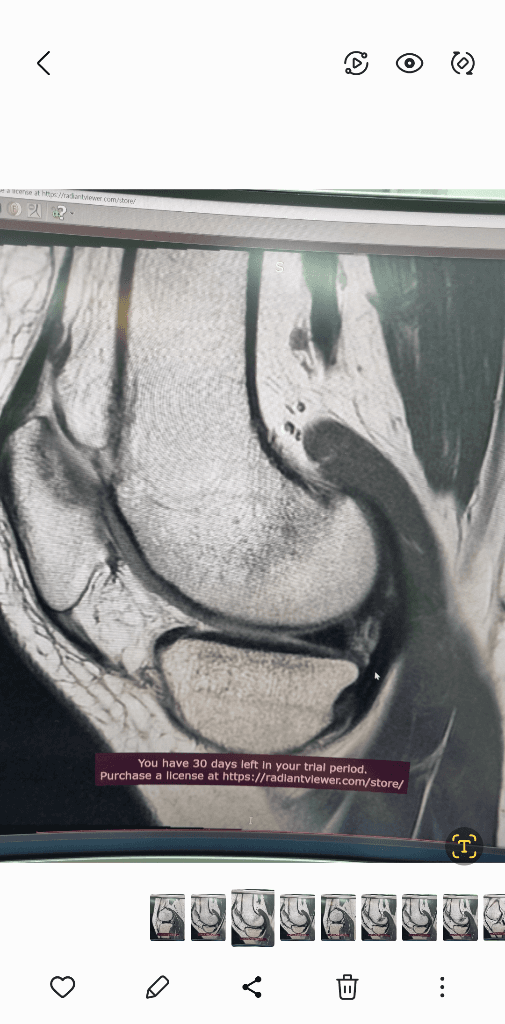

MRI는 신호가 다른 다른 사진들이 있을겁니다.

그런걸 종합적으로 판단해야 정확히 알수 있습니다.

검사한 병원에 판독요청하세요.